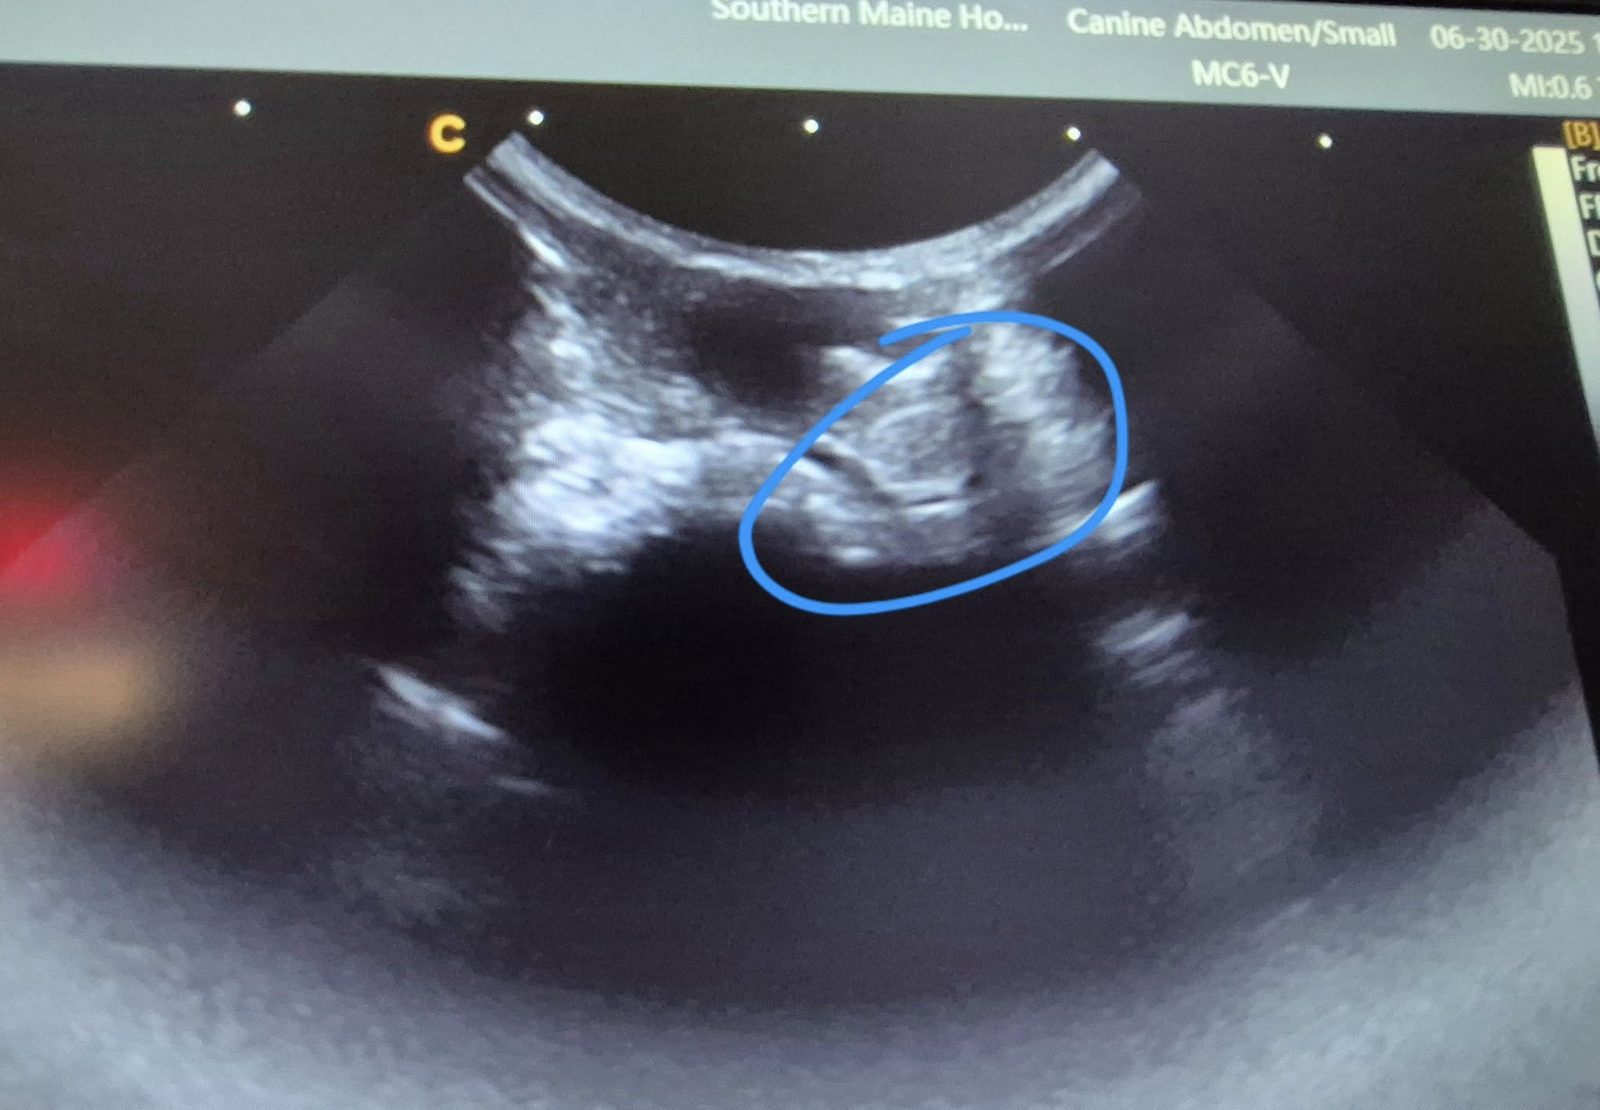

Boba Update!

On October 10, Boba had his surgery at Southern Maine Hospital for Small Mammals, and it was a big success! The tumor was removed with excellent margins, and Boba came through surgery perfectly, eating and pooping as soon as he woke up. The incision is so small and clean, and we're so grateful to Dr Ford for his excellent work! Boba will be recovering with some pain meds for a few days, but we expect him to be back to normal ASAP.

Boba's Incision

Fundraiser for Boba: Help Our Brave Guinea Pig Fight Lymphoma

Meet Boba, a remarkable 7-year-old guinea pig with a heart full of resilience and the spirit of a fighter. Boba has faced more than his fair share of challenges in his life, but he never gave up—and now, he needs our help to overcome his toughest battle yet. Boba has been diagnosed with lymphoma, and he’s scheduled to undergo surgery to remove a cancerous tumor. We are raising funds to cover the cost of his surgery and post-operative care, and every donation—no matter how small—will make a huge difference.